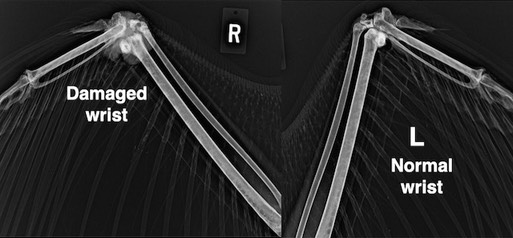

Bald Eagle 22-074

Bald Eagle 22-075